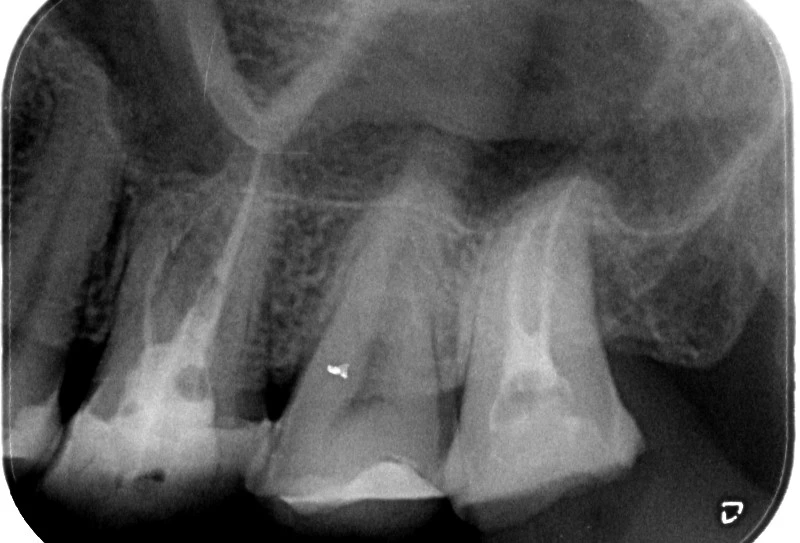

Секторни рентгенографии

Клиниката разполага със съвременен дигитален рентгенов апарат за секторни рентгенографий с минимално облчъване, необходим за целите на денталното лечение -  за отдеференцирането и поставянето на точна диагноза, за екзактно кореново лечение (преди, повреме и след лечението), за проследяване във времето на оздравителният процес след проведеното зъболечение.

Клиниката обслужва с рентгеновият апарат и външни пациенти след предварително записан час.